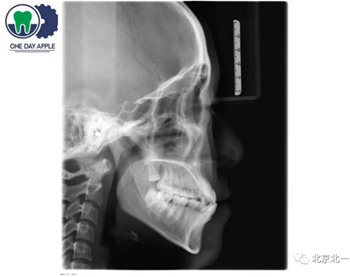

正畸支抗下頜角支抗釘不僅僅考慮解剖結(jié)構(gòu), 需要考慮下頜角骨質(zhì)偏硬, 不助攻可能導(dǎo)致支抗釘無法植入。